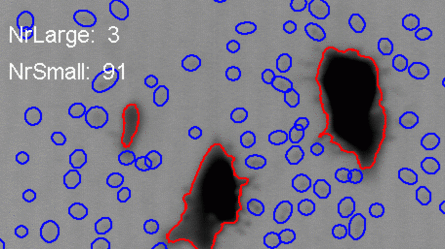

automatically distinguish and count bacteria cultures.

Bacteriology: automatically distinguish and count bacteria cultures.